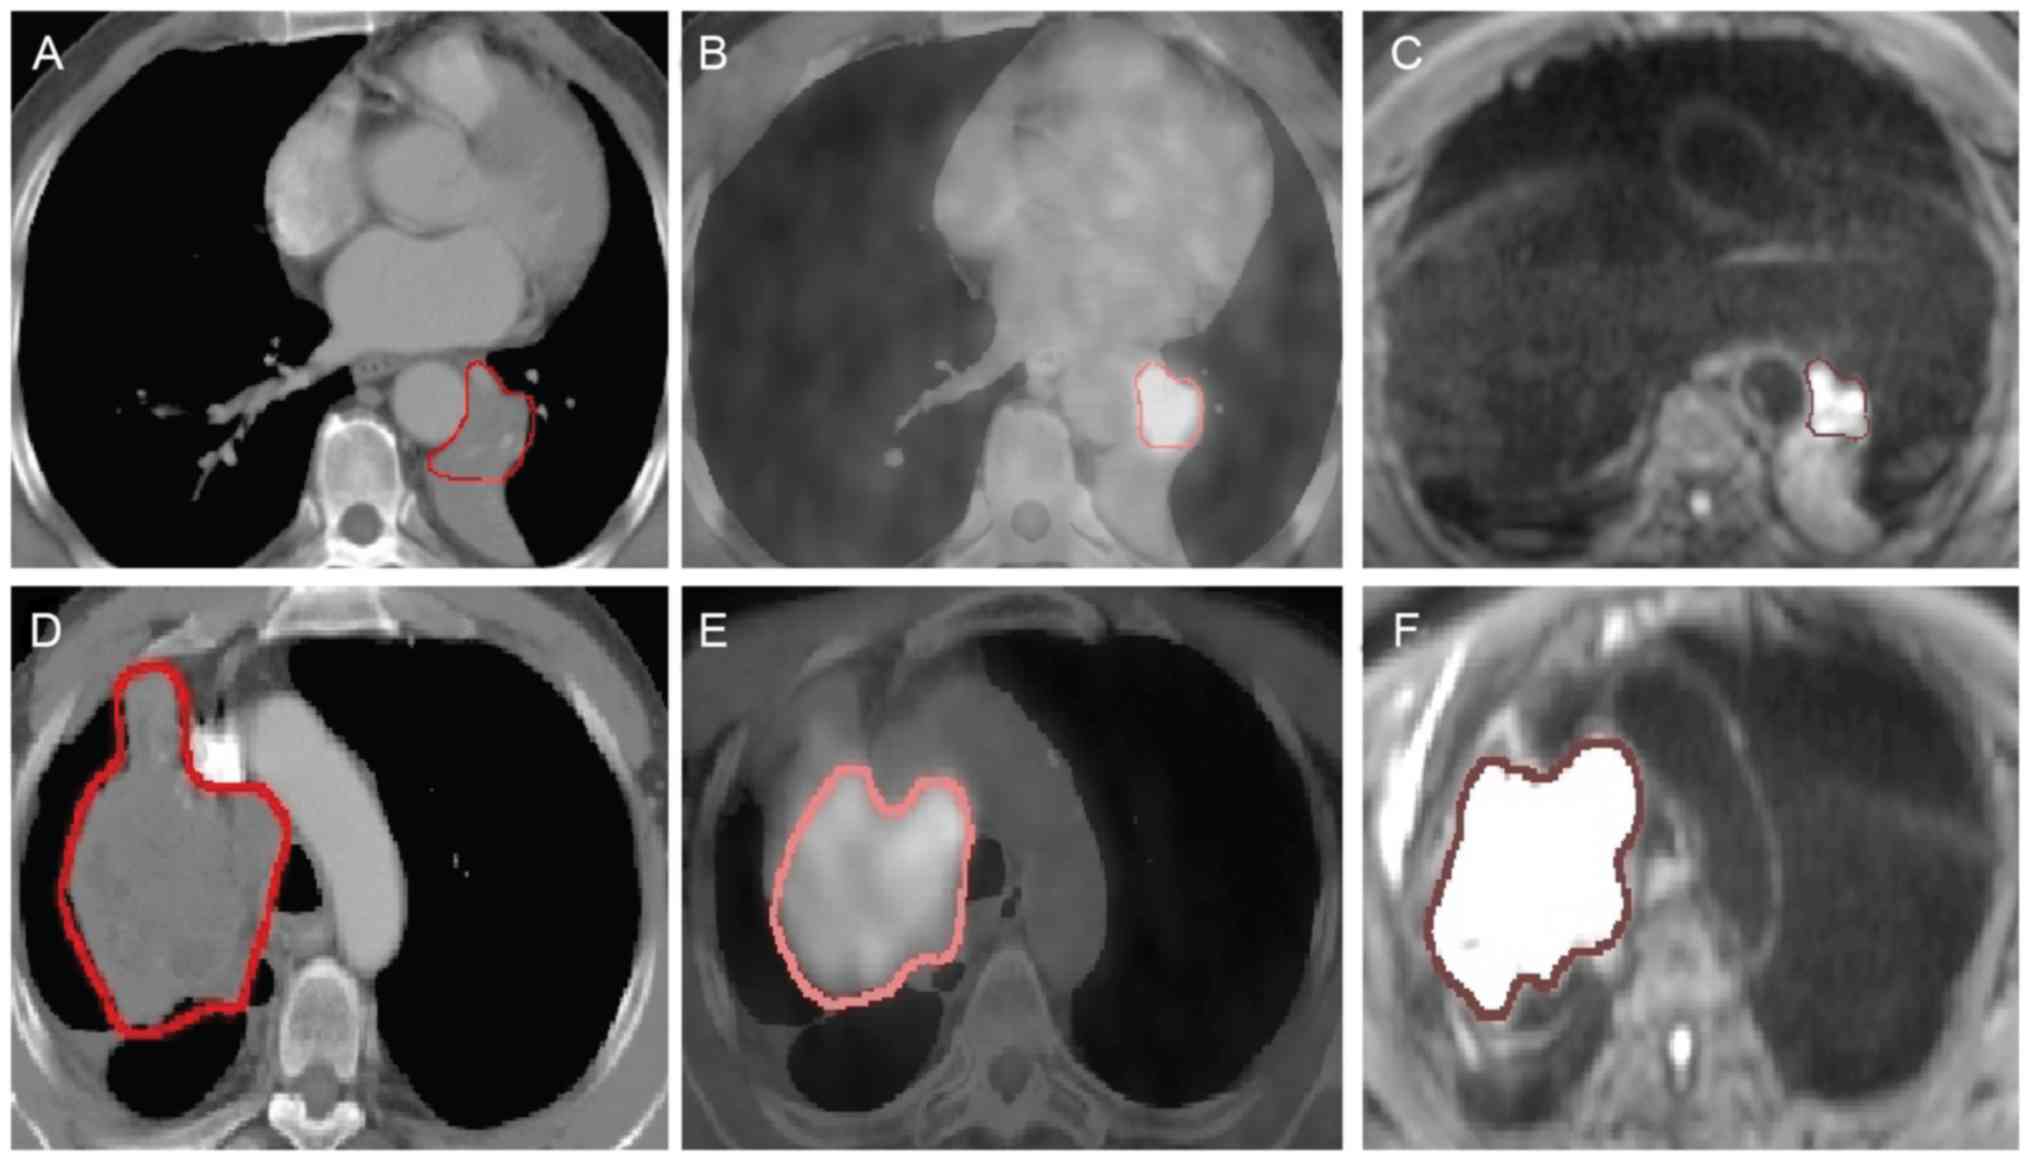

Small Cell Lung Cancer Chest Ct Scan A And Corresponding Pet Ct Download Scientific Diagram

www.researchgate.net